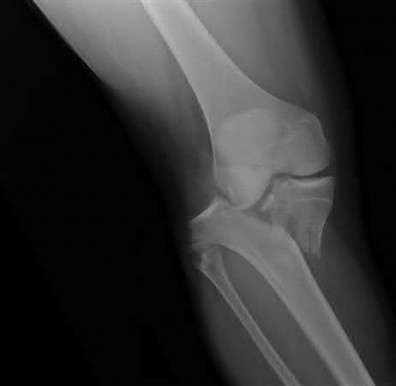

A 38-year-old male suffers the injury shown in Figure A. During operative fixation, free osteoarticular fragments are encountered and reconstruction of these pieces is attempted. Postoperatively, which of the following will have the most beneficial effect on the healing potential of the surviving chondrocytes within these reconstructed articular segments?

Figure A demonstrates a comminuted tibial plateau fracture with significant intra-articular involvement. Basic science evidence has demonstrated that post-operative gentle compressive loading may have a positive impact on articular cartilage healing; however, excessive shear loading may be detrimental.

Irrgang et al provide guidelines for rehabilitation following surgical management of articular cartilage lesions of the knee. They state that after articular cartilage repair, exercises to enhance muscle function must be done in a manner which minimizes shear loading of the joint surfaces in the area of the lesion. The authors also discuss the benefits of gentle compressive loading and motion of the joint, and its positive effects on chondrocyte nutrition.

Furthermore, they recommend a period of protected weight bearing as often being necessary, and that this should be followed by progressive loading of the joint.

Illustration A is a diagram showing the different layers of joint cartilage.